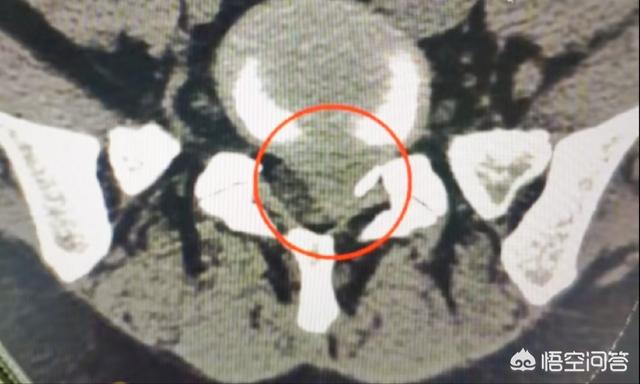

軽度から中等度の椎間板ヘルニアは非常に回復しやすいのですが、重度のヘルニアになると、椎間板の中心にある髄核が後縁の線維性環状組織や後縦靭帯までも突き破ってしまうため、時間の経過とともに回復するのが非常に難しくなります。下は重度の椎間板ヘルニアの患者のCT画像です:

椎間板ヘルニアは部分的に回復することはあるが、「完全に回復した」とは言い難い。医学の世界には「臨床的治癒」という言葉がある。つまり、完治しない病気でも、不快感などの症状がなくなり、日常生活に支障がなくなれば、臨床的治癒といえるが、さまざまな指標を見ると、発病前と一定の違いがあり、ある指標、データ、検査結果などは、まだ正常ではない状態にある。ある指標、データ、検査結果などはまだ異常な状態にある。